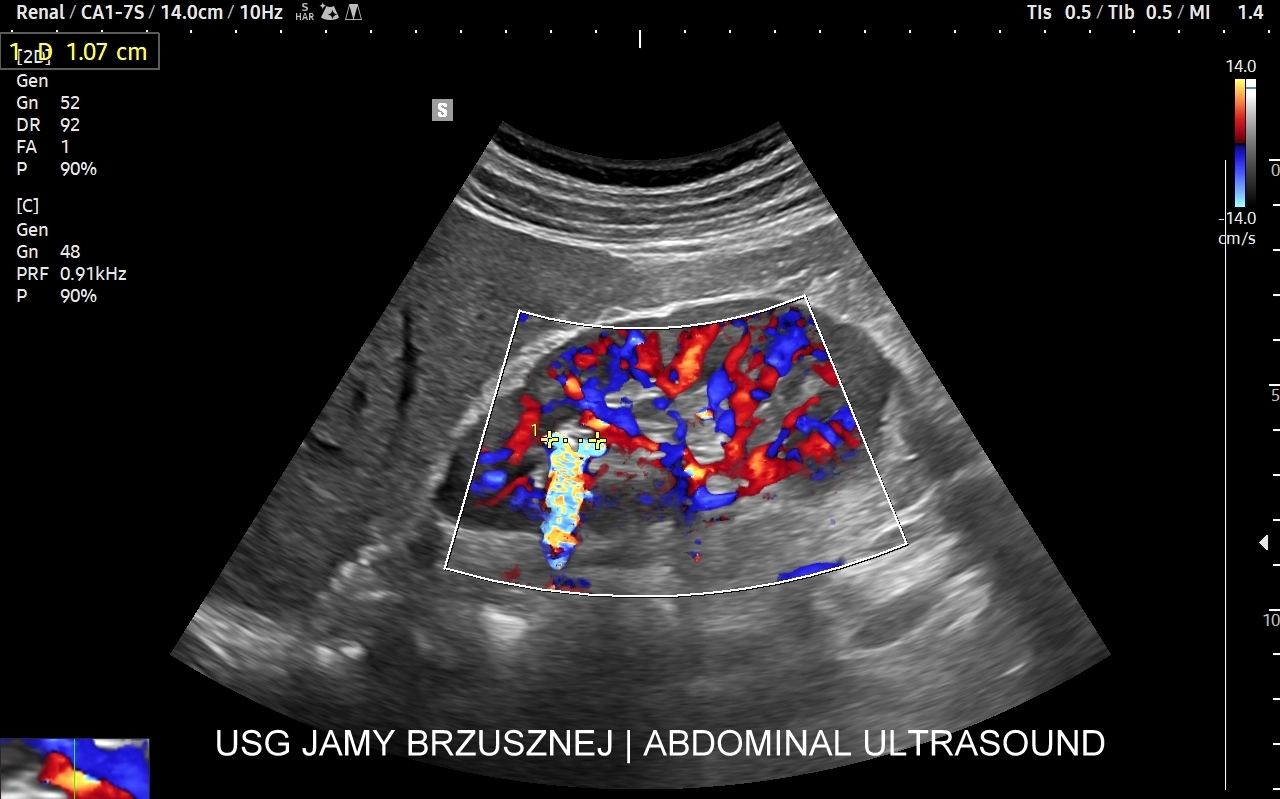

Badanie multiparametryczne MPUS jamy brzusznej

Rozwinięciem standardowego badania USG jamy brzusznej jest badanie multiparametryczne MPUS (ang. multiparametric ultrasound), w ramach którego wykorzystuje się różnorodne, nowoczesne modalności sonograficzne, takie jak tryby mikrounaczynienia MVI, B-flow, elastografię, ilościową ocenę stłuszczenia wątroby QUS, czy tryb Dopplera spektralnego, a to wszystko w celu uzyskania dodatkowej oceny funkcjonalnej i biologicznej struktur, narządów oraz tkanek jamy brzusznej. Obrazowanie MPUS niejednokrotnie poprawia także wizualną ocenę narządów wewnętrznych, czego przykładem jest zastosowanie trybu MVI w ramach bezkontrastowej angiografii sonograficznej naczyń oraz w ocenie guzów nerek. Klasycznymi i najczęstszymi zastosowaniami badania MPUS są jednakże funkcjonalna ocena wątroby w kierunku stłuszczenia, zwłóknienia, zapalenia i nadciśnienia wrotnego, a także ocena żywotności i funkcji nerek.

• Możliwość rozszerzenia zakresu badania USG w razie wystąpienia konieczności. Praktycznymi przykładami są zastosowanie trybu MVI w przypadku wykrycia guzka w nerce, czy przeprowadzenie badania elastograficznego i dopplerowskiego w wypadku stwierdzenia nieprawidłowego obrazu wątroby.